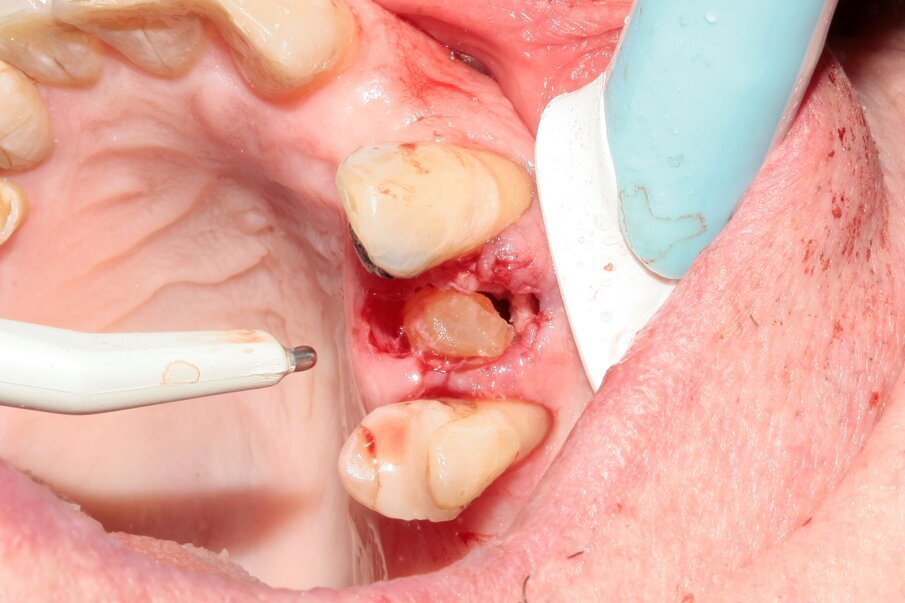

A 70-year-old female patient visited our clinic owing to a fractured maxillary first molar. Tooth #24 had previously had a large composite restoration that was no longer in place at the time of the dental appointment.

Tooth #24 was severely decayed down to the marginal bone edge.

Figs. 2–4: The tooth was luxated with Luxator P4 (dual edge, lilac).